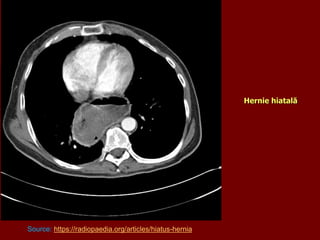

HERNII HIATALE

Hernie hiatală

Source: https://radiopaedia.org/articles/hiatus-hernia